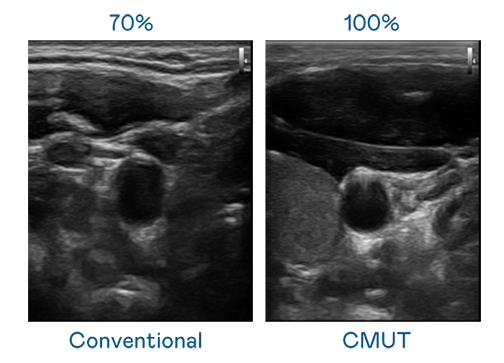

CMUT 技术是一种用电容式微机电元件来产生超音波讯号的技术。与传统 PZT 压电式技术相比,CMUT 频宽增加 30%,更宽频的超音波讯号让影像解析度大幅提升,是实现高影像品质医疗超音波扫描、促进精准医疗发展的关键技术。

大频宽带来超清晰影像

超音波影像的解析度高低,首先取决于探头能发出的讯号频宽。永利yl23411 CMUT 可提供高清晰的超音波讯号,提供高频宽、高灵敏度、影像纹理细节更高的超音波影像,协助医护人员缩短影像判读时间及利用精准的医疗影像进行诊断。